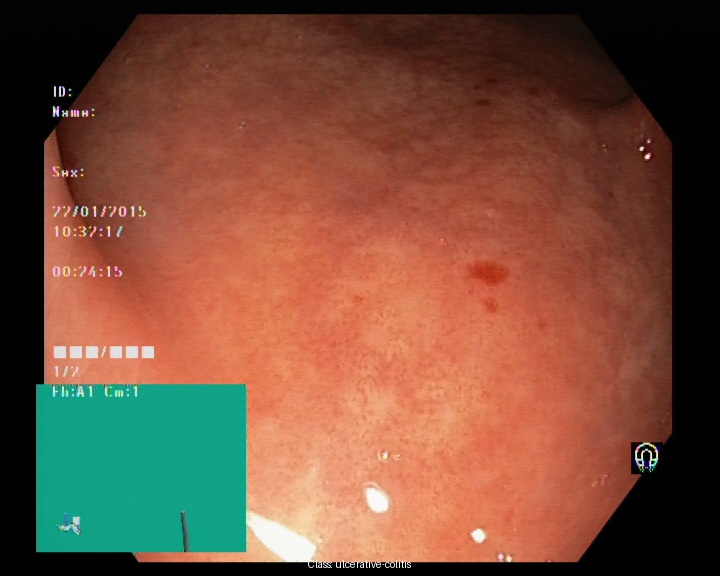

Kvasir dataset serves as a widely recognized resource for research in automated gastrointestinal (GI) disease detection [12]. It contains labeled endoscopic images representing a range of GI conditions, including both healthy and pathological cases. Its diversity in anatomical regions and pathological categories makes it a valuable benchmark for training machine learning models aimed at GI disease classification. The dataset has 8000 images belonging to 8 different classes namely dyed-lifted-polyps, dyed-resection-margins, esophagitis, normal-cecum, normal-pylorus, normal-z-line, polyps, ulcerative-colitis. Figure 1 depicts the sample images from the dataset. Despite its extensive coverage, the dataset poses challenges such as variations in lighting, differences in image quality, and visual similarities between certain categories, which may affect model performance and classification accuracy.

| (a) | (b) | (c) | (d) |

| (e) | (f) | (g) | (h) |